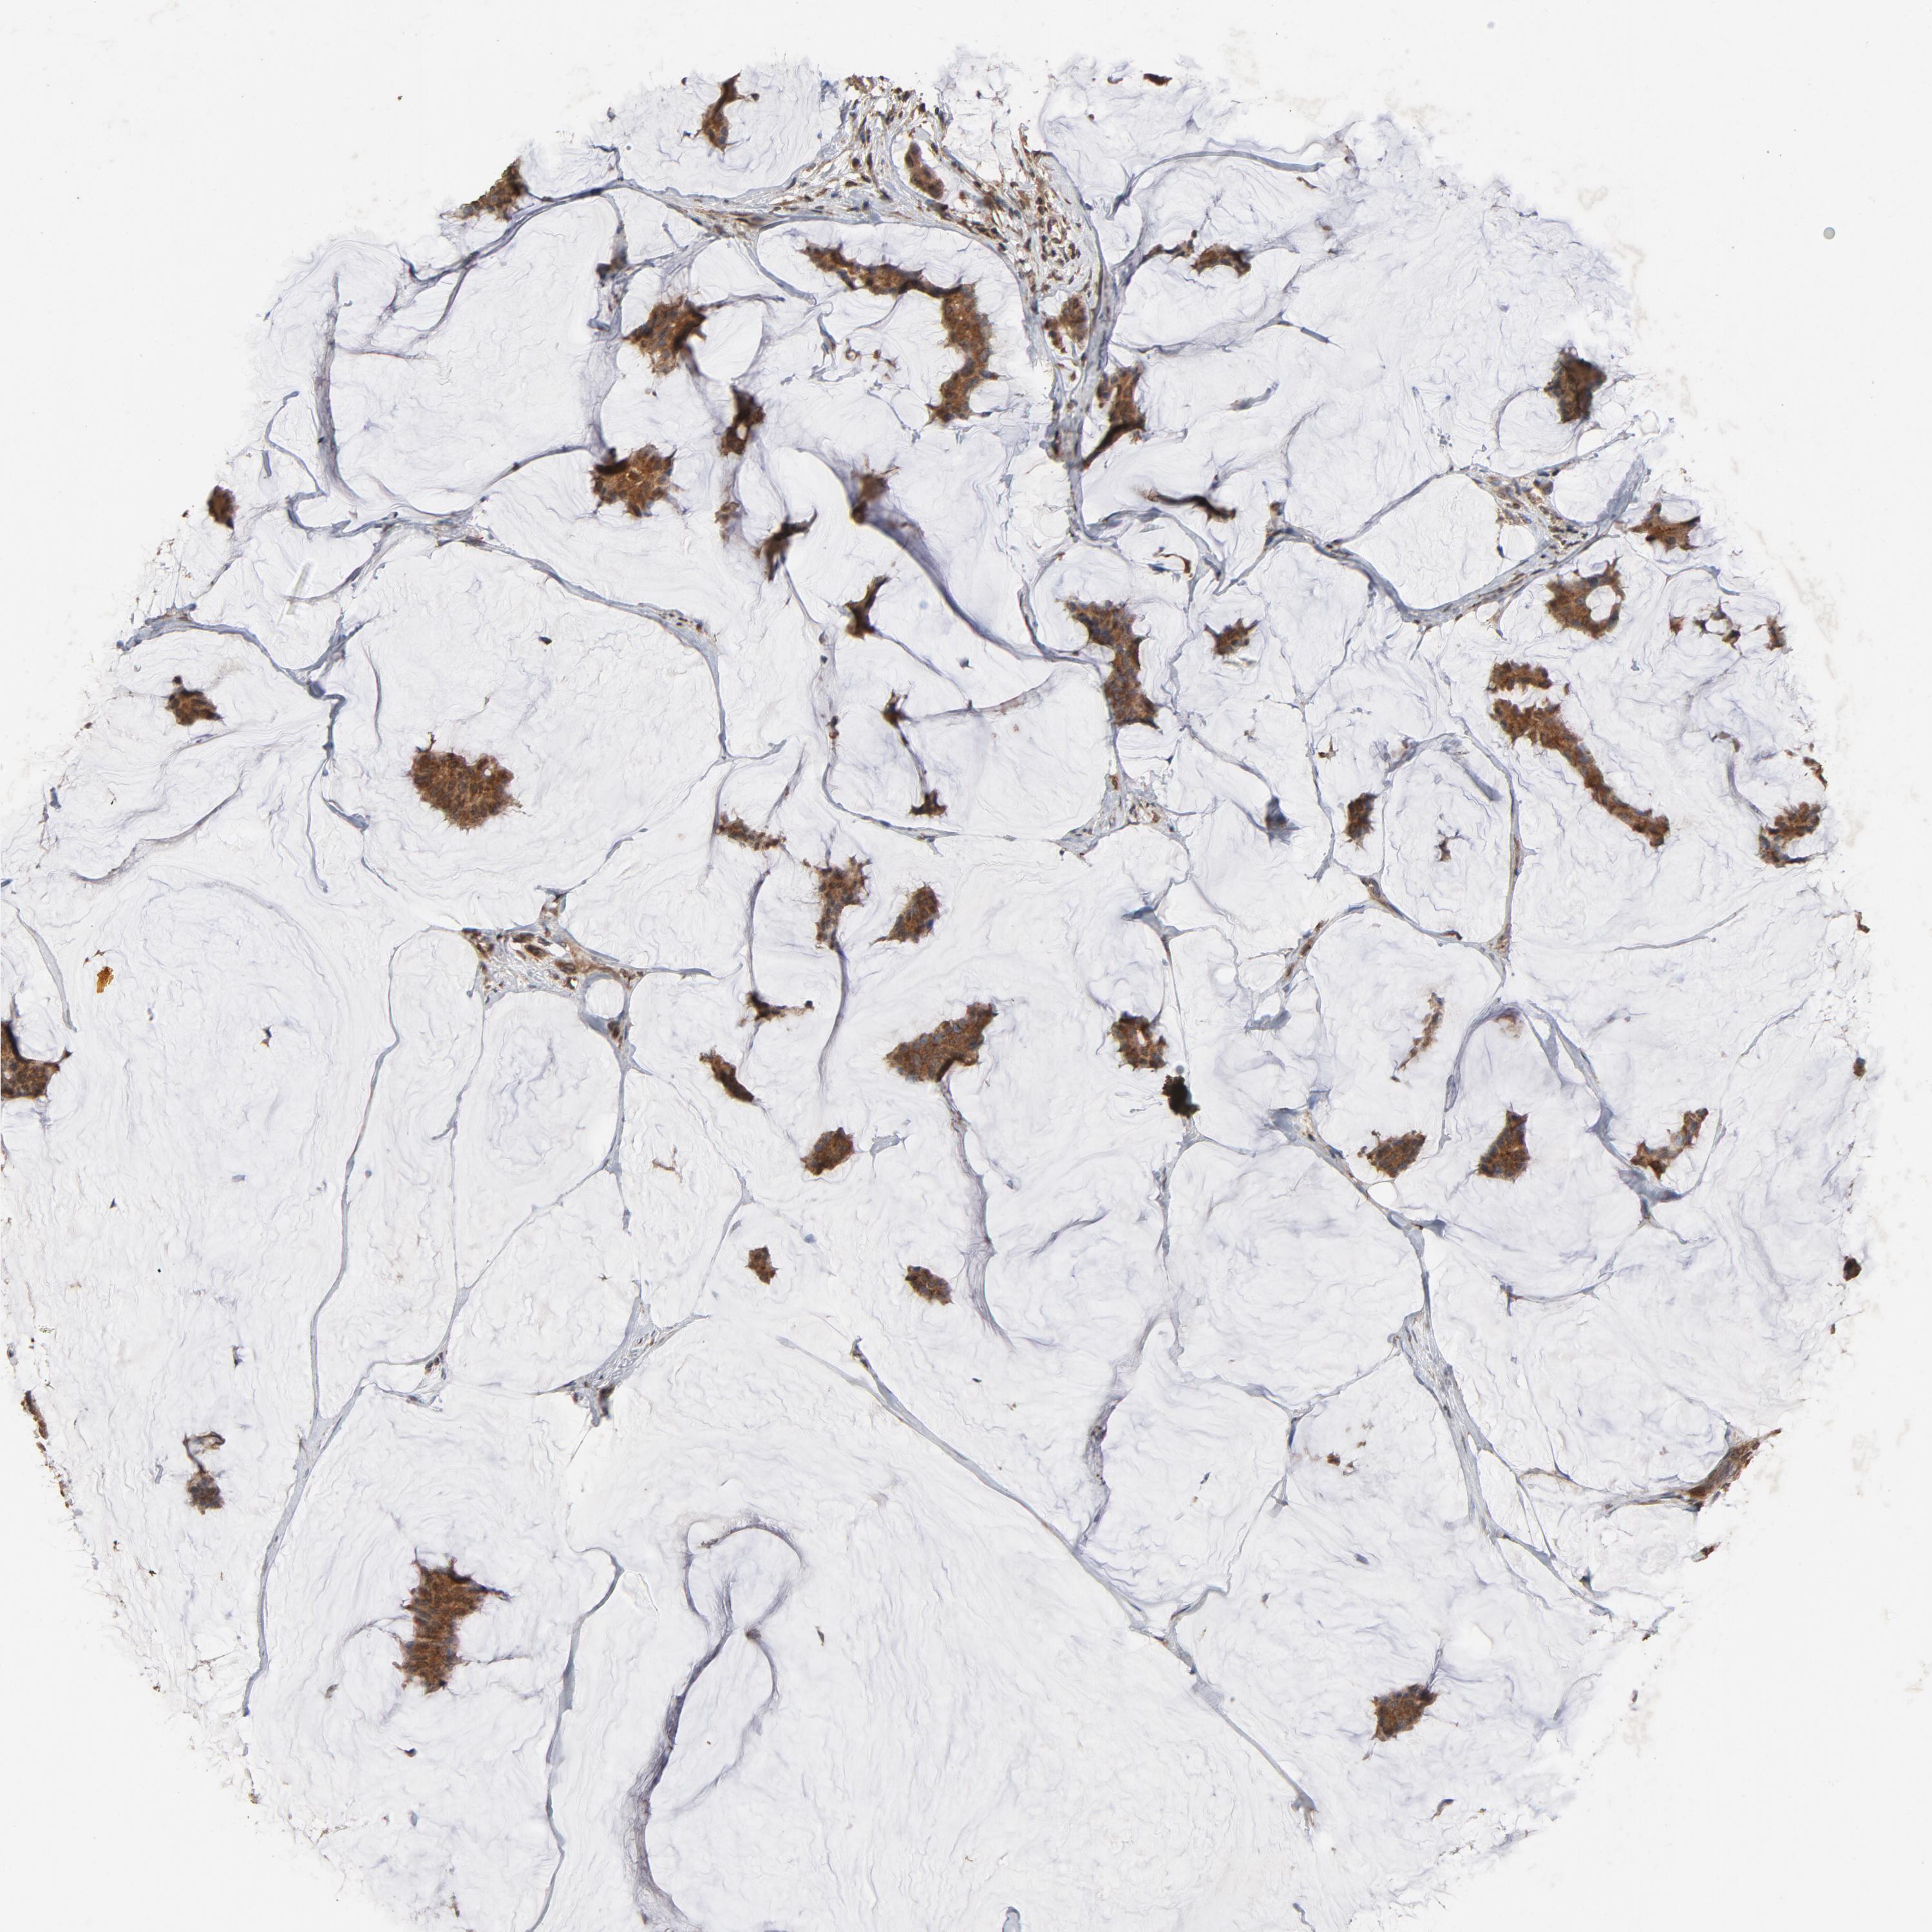

CDC42

CANCER BREAST CANCER Show tissue menu

BRCA TCGA BRCA VALIDATION PROTEIN EXPRESSION